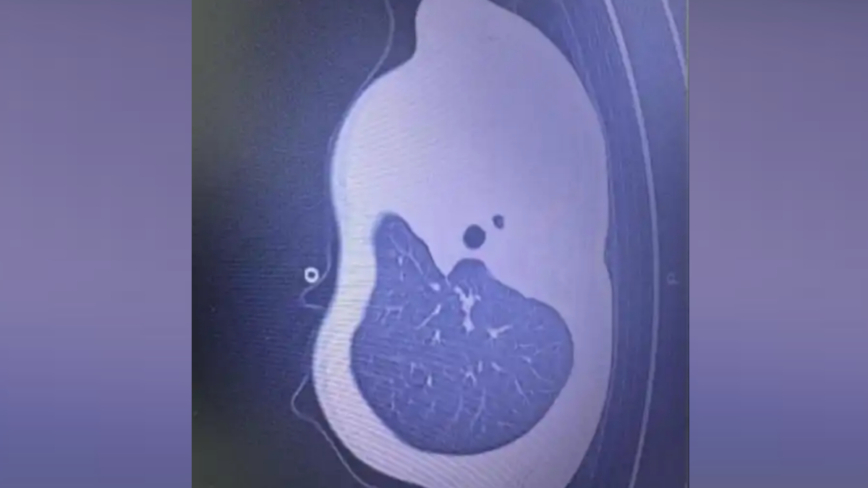

12月2日早上,小宇呼吸急促、嘴唇發紫、精神不振,家人急忙將他送到浙江大學醫學院附屬兒童醫院急診。經檢查,驗血顯示炎症指標大幅上升,胸片更發現左側肺葉幾乎「不工作了,影像中變成大片白色」,就是所說的「白肺」。

浙江大學醫學院附屬兒童醫院PICU副主任楊子浩主任醫師表示,這是流感合併細菌感染引起的嚴重肺炎,同時發生壞死性喉氣管支氣管炎,一種嚴重併發症:黏稠痰栓會像樹枝一樣堵在氣道分支處,導致肺部無法正常通氣,若不及時處理,幾小時就可能威脅生命。

當天中午,小宇被緊急送進PICU。下午4點多,醫生做了氣管鏡,鏡下畫面比預期的還要嚴重:氣道裡堵滿了樹枝狀的黏稠痰栓,呼吸通道完全被塞住,氣道內壁還有壞死組織。